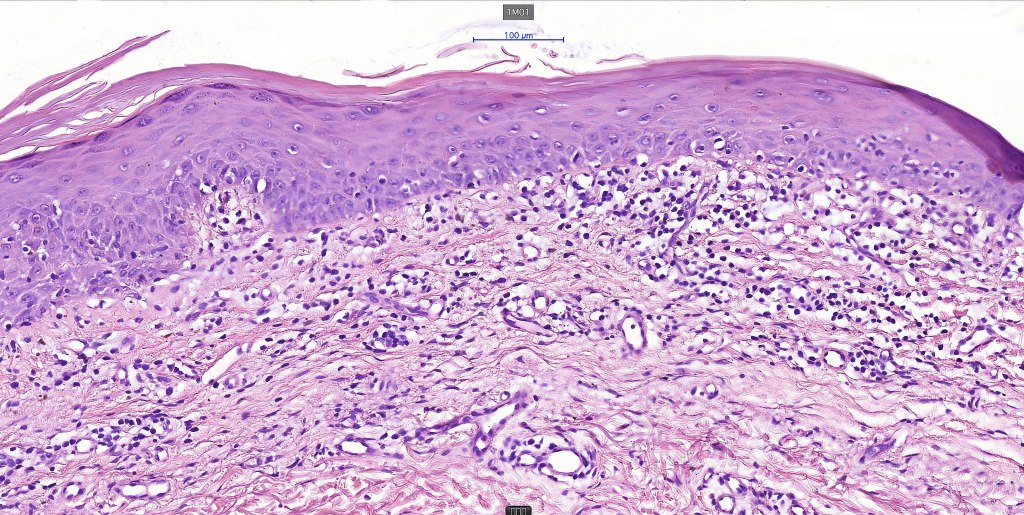

Histological features

The histological hallmark of mycosis fungoides is the presence of large atypical lymphocytes with a convoluted/cerebriform nuclear border (Sézary cells). These may be found at the epidermal-dermal jnuction and as collections within the epidermis (Pautrier microabscess). These are most easily found in plaque stage disease. The epidermal component can be subtle in patch stage disease and is often lost in tumor stage dsease. The classification into patch, plaque & tumor stage disease is less helpful histologically as the features merge from one to the other. It is all a matter of degree.

Patch stage disease

•Changes can be subtle & dependent on clinicopathological correlation; in many patients sequential biopsies over many months may be necessary to establish the diagnosis.

•Mild hyperkeratosis & focal parakeratosis, acanthosis, epidermal atrophy or of normal thickness

•Superficial dermal lymphocytic infiltrate containing variable numbers of Sézary cells with atypical, irregular, hyperchromatic nuclei surrounded by a halo; these can be very few in number and dependant on viewing multiple levels

•Palisading of atypical lymphocytes along the epidermal-dermal border

•Pautrier microabscesses may be present but are often absent in patch stage disease

•Variable interface change with keratinocyte necrosis & pigmentary incontinence

•Eosinophils & plasma cells sometimes present

•Coarse collagen bundles in the papillary dermis can be a feature but this is not as marked as seen in plaque disease

.Although in typical mycosis fungoides fungoides, spongiosis is absent, exceptionally it can be a feature